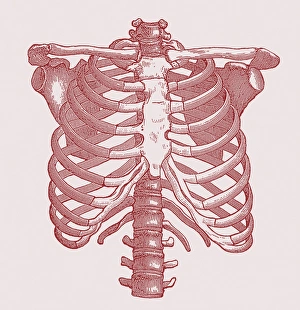

The scapula, also known as the shoulder blade, is a crucial bone in our body that plays a significant role in our mobility and stability. It forms part of the pectoral girdle and connects the upper arm to the thorax. When we examine diagrams of the bones of the hand and arm, we can see how intricately connected they are to the scapula. This connection allows us to perform various movements with precision and control. In an anterior view total shoulder joint repair image, we witness medical advancements aimed at restoring functionality to this vital joint. The intricate procedure highlights just how important it is to maintain a healthy scapula for optimal movement. Shoulder muscles artwork showcases their attachment points on the scapula, emphasizing their role in providing strength and stability during physical activities. Understanding these muscles helps us appreciate their contribution to everyday tasks like lifting or throwing. A front view of female anatomy highlighting the endocrine system reminds us that even though not directly related to the scapula, every part of our body works together harmoniously. Hormones secreted by glands within this system influence bone health and development. An anterior view of human skeletal system with labels gives us a comprehensive understanding of where exactly our scapula fits into this complex framework. It serves as an anchor point for numerous ligaments and tendons essential for proper functioning. Pictograms on an ox scapula depict ancient rituals performed to ward off danger—a testament to how cultures throughout history recognized its significance beyond mere anatomy. These artifacts remind us that humans have long understood its importance in daily life. The skeleton of an eagle after Milne-Edwards engraving demonstrates nature's adaptation at its finest—the bird's wingspan relies heavily on strong shoulder blades (scapulas) allowing it effortless flight through vast skies. Haydon's Curtius engraving captures another artistic representation showcasing human form—this time focusing on muscular structure including the scapula.